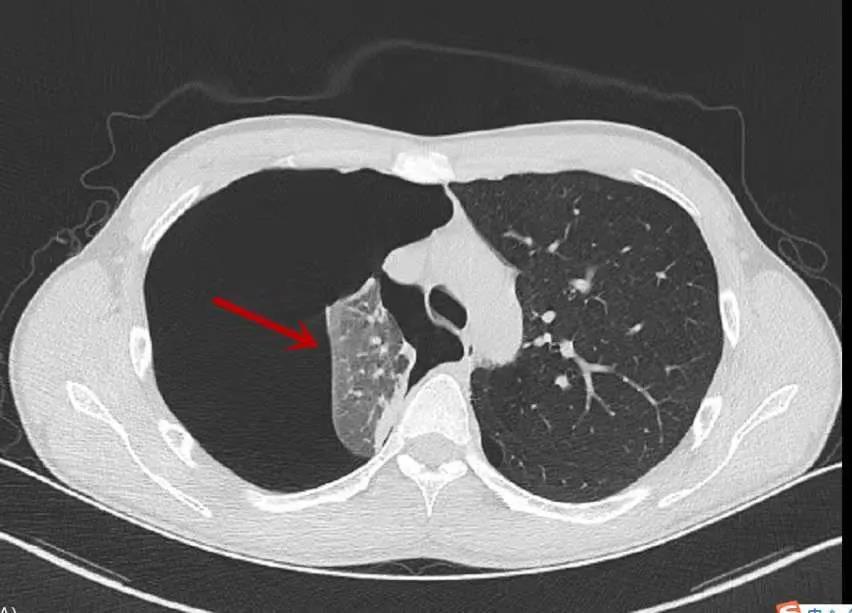

胸部CT显示,小乐右肺犹如被戳破的气球瘪了下去,肺组织压缩达90%,属于典型的自发性气胸,若不及时抢救会危及生命。

箭头所指为压缩至正常十分之一的肺(浙江省人民医院供图)